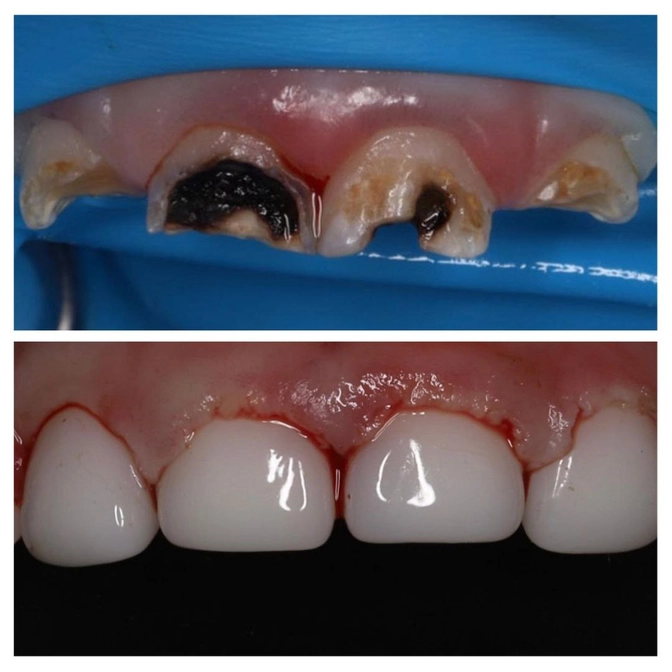

Агрессивный кариес раннего детского возраста

Начинается с появления белых полосок на внутренней стороне верхних передних зубов и/или в пришеечной зоне с внешней стороны.

Разрушение стремительное!

Кариес "сожрал" зубки малыша больше, чем наполовину.

Тянуть-откладывать нельзя, т.к. есть риск их потерять!

Зубки разрушены очень сильно, но их не пришлось удалять! Ольге Царьковой удалось их восстановить!

Теперь малыш может улыбаться без стеснения. А зубки должны прослужить до естественной смены.